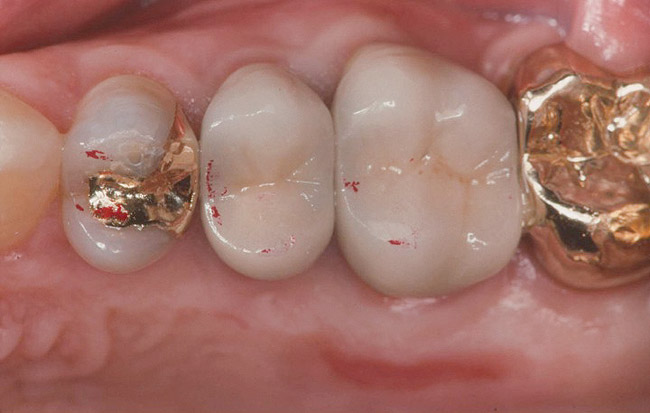

Figure 4. Occlusal contacts occur generally on the posterior teeth, most often on the first molars, followed by the second molars and premolars.

Figure 4

Loss of tooth contact or near contact78,79 on one quadrant of the mouth has the potential for dysfunction and perhaps even lasting damage to the musculature, not just on the noncontact side, but on both sides.80 Tooth contact during maximal force chewing is the same as in static maximum force intercuspal contact,81 indicating the role stable functional tooth contacts play in optimal muscle function. However, not all of the teeth have contact in maximum intercuspation.82,83 Moreover, most of the contacts that do occur are in the molar region, and, not surprisingly, the greatest forces of contact are also found posteriorly (Figure 4).84 It can be inferred that one of the functions of the posterior teeth is to hold the infero-superior component of vertical dimension, and in some cases (ie, group function), the medio-lateral vector as well.